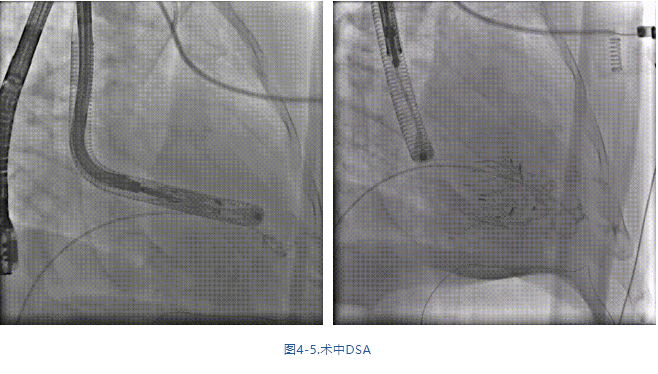

手術在全麻狀態下進行,采用經右側頸靜脈入路,在TEE和DSA的指引下緩慢送入輸送器進入體內,進入右室后釋放室間隔錨定裝置,旋轉輸送器,使得錨定裝置對準室間隔面;釋放前瓣夾持件,確定夾持件位于右室側后釋放人工瓣膜盤片,DSA及超聲確認盤片位于右房側,并適時調整瓣膜的同軸性。在DSA和超聲的監視下調整室間隔錨定件貼合室間隔,釋放室間隔錨定裝置。再次確認瓣膜的穩定性和同軸性后,將輸送器撤出體內,最終完成瓣膜植入(圖4-5),手術室即刻拔除氣管插管。術后超聲提示人工三尖瓣同軸性良好,瓣架固定牢靠,無反流和瓣周漏,術后三尖瓣平均跨瓣壓差顯著降低。